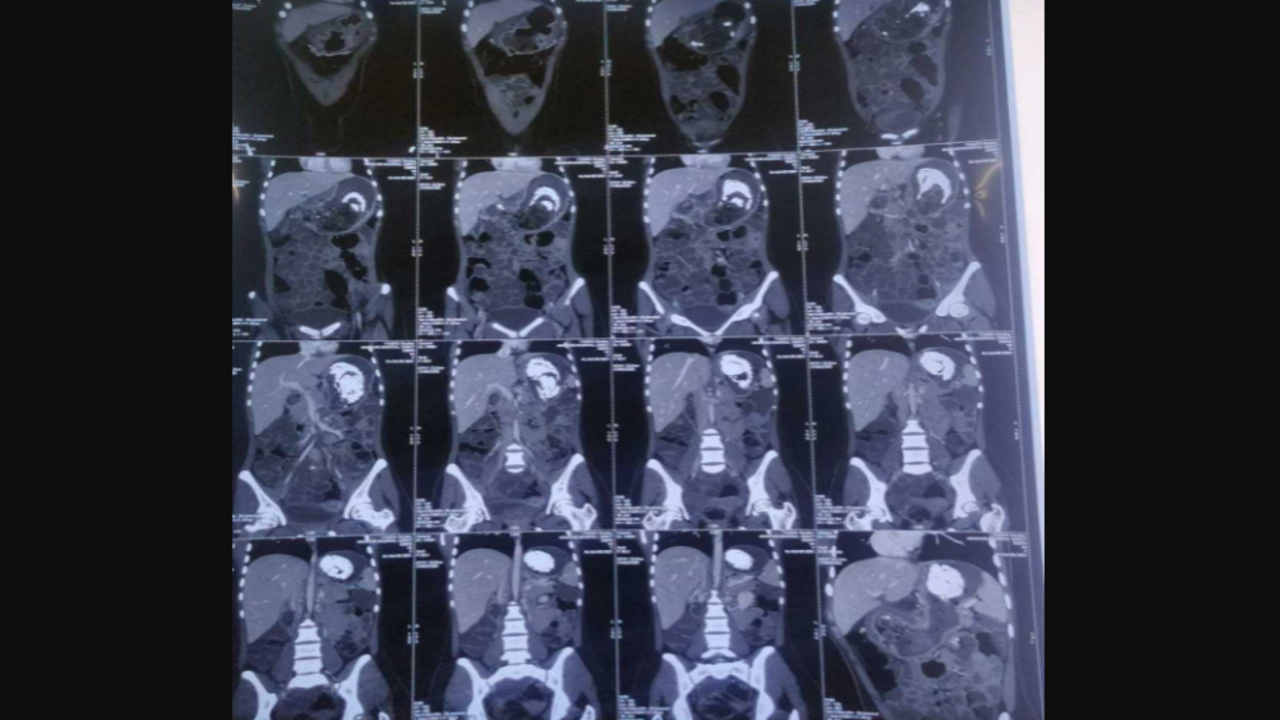

SURAT: A hairball weighing around 500 gram was removed from the stomach of a girl studying in Class XI. The surgery was performed at New Civil Hospital (NCH).

The 16-year-old girl, a resident of Ghod Dod Road area, had stopped eating properly which led to her losing weight. Noticing a change in her food intake, her family got the girl examined at a private clinic. Medical examinations revealed a hairball in her stomach. The doctors suggested surgery to avoid further health issues.

<p> Medical examinations revealed a hairball in her stomach.</p>